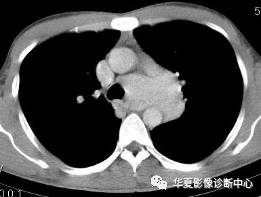

男性,32岁。无明显原因胸闷不适3月,胸片示纵隔及左肺门占位。

【CT征象】纵隔主肺动脉窗内见团状软组织肿块,最大截面约5.0cmX4.0cm,密度均匀,动脉期呈中度强化,延迟扫描呈明显强化,接近同期血管密度;左肺动脉干及左主支气管略受压。

【CT诊断】 ①巨淋巴结增生症;②淋巴瘤;③结节病;④淋巴结结核。

【最后诊断】纵隔巨淋巴结增生症。